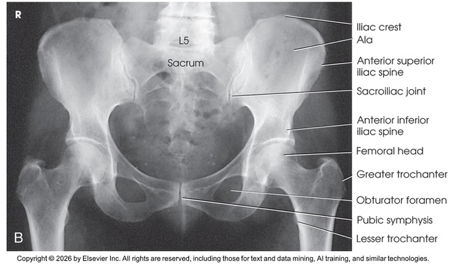

AP Projection; Pelvis and Proximal Femora (Labeled)

AP Projection; Pelvis and Proximal Femora (Eval Criteria)

• Evidence of proper collimation

• Entire pelvis along with the proximal femora

• Both ilia and greater trochanters equidistant to the edge of the radiograph

• Lower vertebral column centered to the middle of the radiograph

• No rotation of pelvis

o Both ilia symmetric in shape

o Symmetric obturator foramina

o Ischial spines equally seen

o Sacrum and coccyx aligned with the pubic symphysis

• Proper rotation of proximal femora

o Femoral necks in their full extent without superimposition

o Greater trochanters in profile

o Lesser trochanters, if seen, visible on the medial border of the femora

• Soft tissue and bony trabecular detail

Note: Rotate lower limbs 15 to 20 degrees internally. *Must include about ¼ or 1/3 of upper femurs